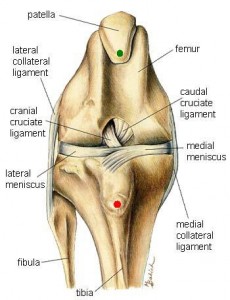

There are two ligaments inside the knee that cross – hence the name cruciate ligament. These ligaments provide knee stability for your pet while walking, running, playing ball, etc. If the anterior cruciate tears (the front most ligament and most commonly injured), the shinbone moves forward as the dog walks causing pain and damage to the cartilage in the knee. Torn ligaments in the knee occur in animals just as they do in humans. Rupture of the cruciate ligament may be caused in a healthy joint by a traumatic incident, or it may be the result of gradual weakening of the ligament due to predisposing factors such as being overweight, pre-existing inflammation, and predisposing genetic factors. A torn cruciate ligament results in muscle atrophy, joint scar tissue, arthritis, and reduced joint range of motion. Physical rehabilitation helps to reverse these changes and return the leg back to pre-injury function.

Cruciate ligament ruptures are diagnosed based upon history, symptoms and palpation of the joint with the patient under sedation. When the patient is sedated, the muscles relax and the veterinarian can move the tibia back and forth under the femur. If the knee moves, it is a positive drawer motion and that means that the cruciate ligament is torn or ruptured. Following this palpation, as part of the evaluation for TPLO or Tibial Tuberosity Advancement (TTA) surgery, the knees are x-rayed as well.